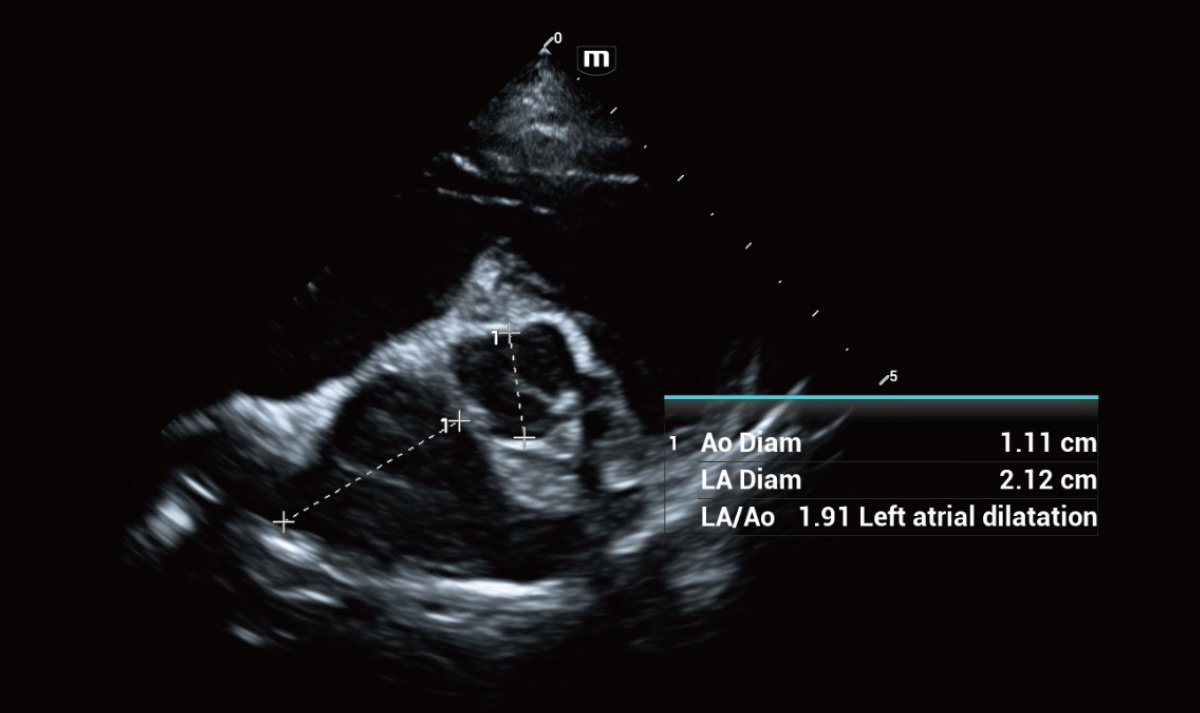

Solución de cardiología

Indicar condiciones clínicas potenciales o sospechadas inmediatamente.